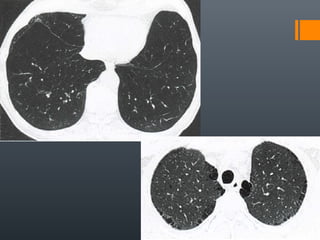

O documento discute vários conceitos radiológicos incluindo consolidação, atelectasia, nódulos, pseudocavidades e padrões intersticiais, fornecendo definições, sinais e diagnósticos diferenciais para cada tópico. Ele também discute a redução da atenuação pulmonar e fornece um link para mais informações.